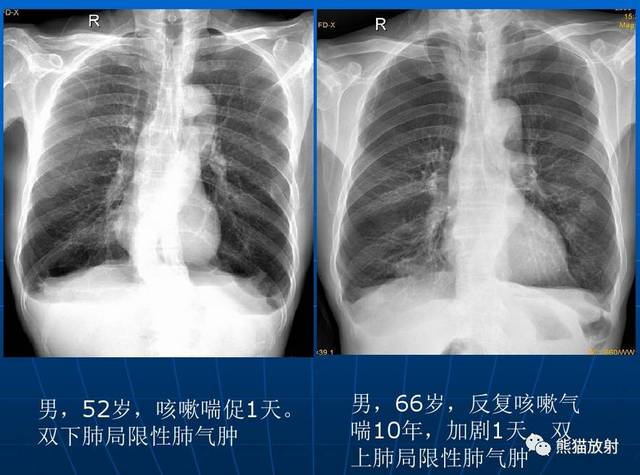

肺气肿x线表现,肺气肿x线图片

肺气肿x线图片

肺气肿胸片

肺气肿的x线表现图片

肺气肿x线胸片特征

肺气肿x线图片dr